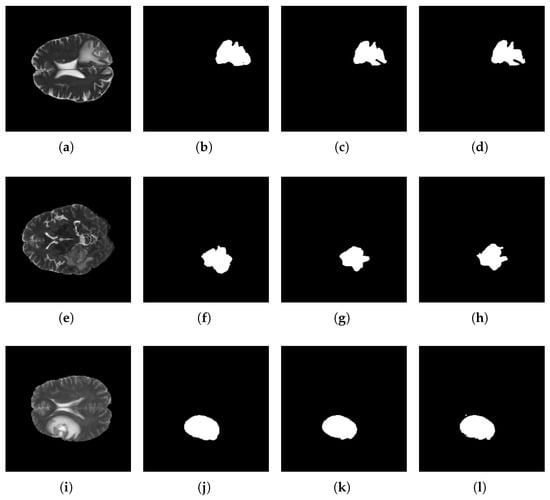

5.3. Segmentation Results

5.4. Discussion